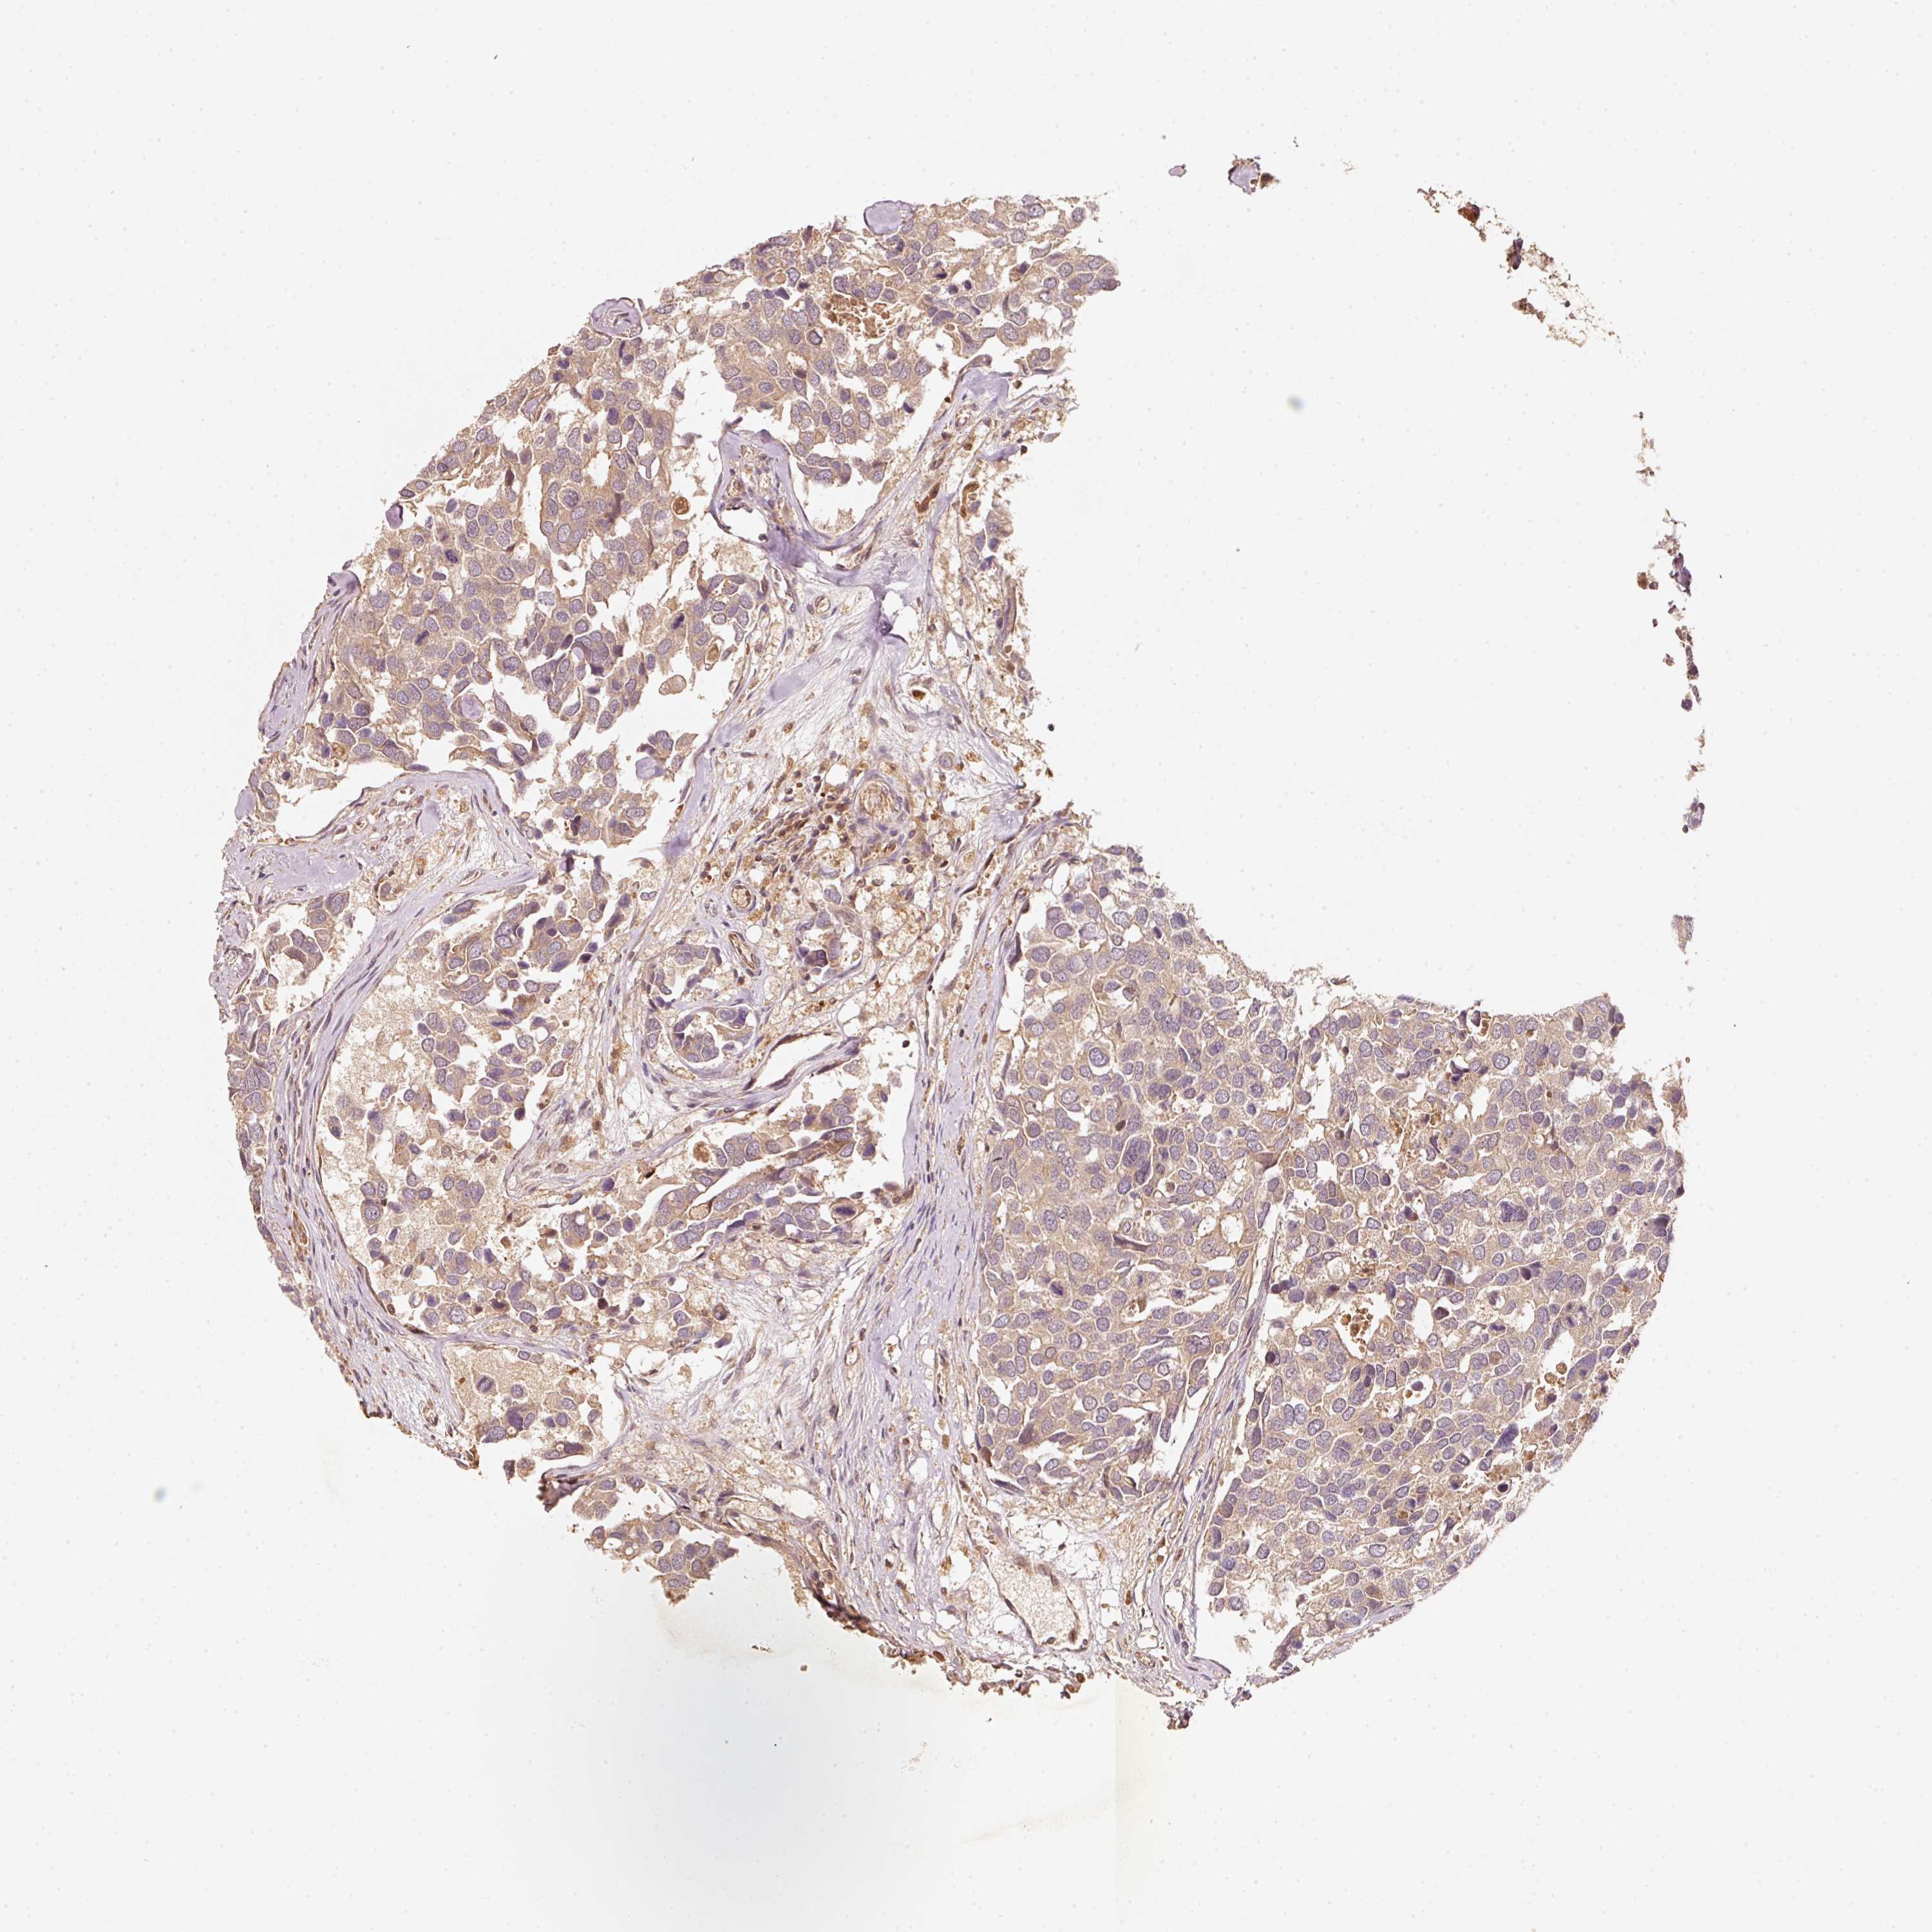

CANCER BREAST CANCER Show tissue menu

BRCA TCGA BRCA VALIDATION PROTEIN EXPRESSION

Breast cancer

Human cancer